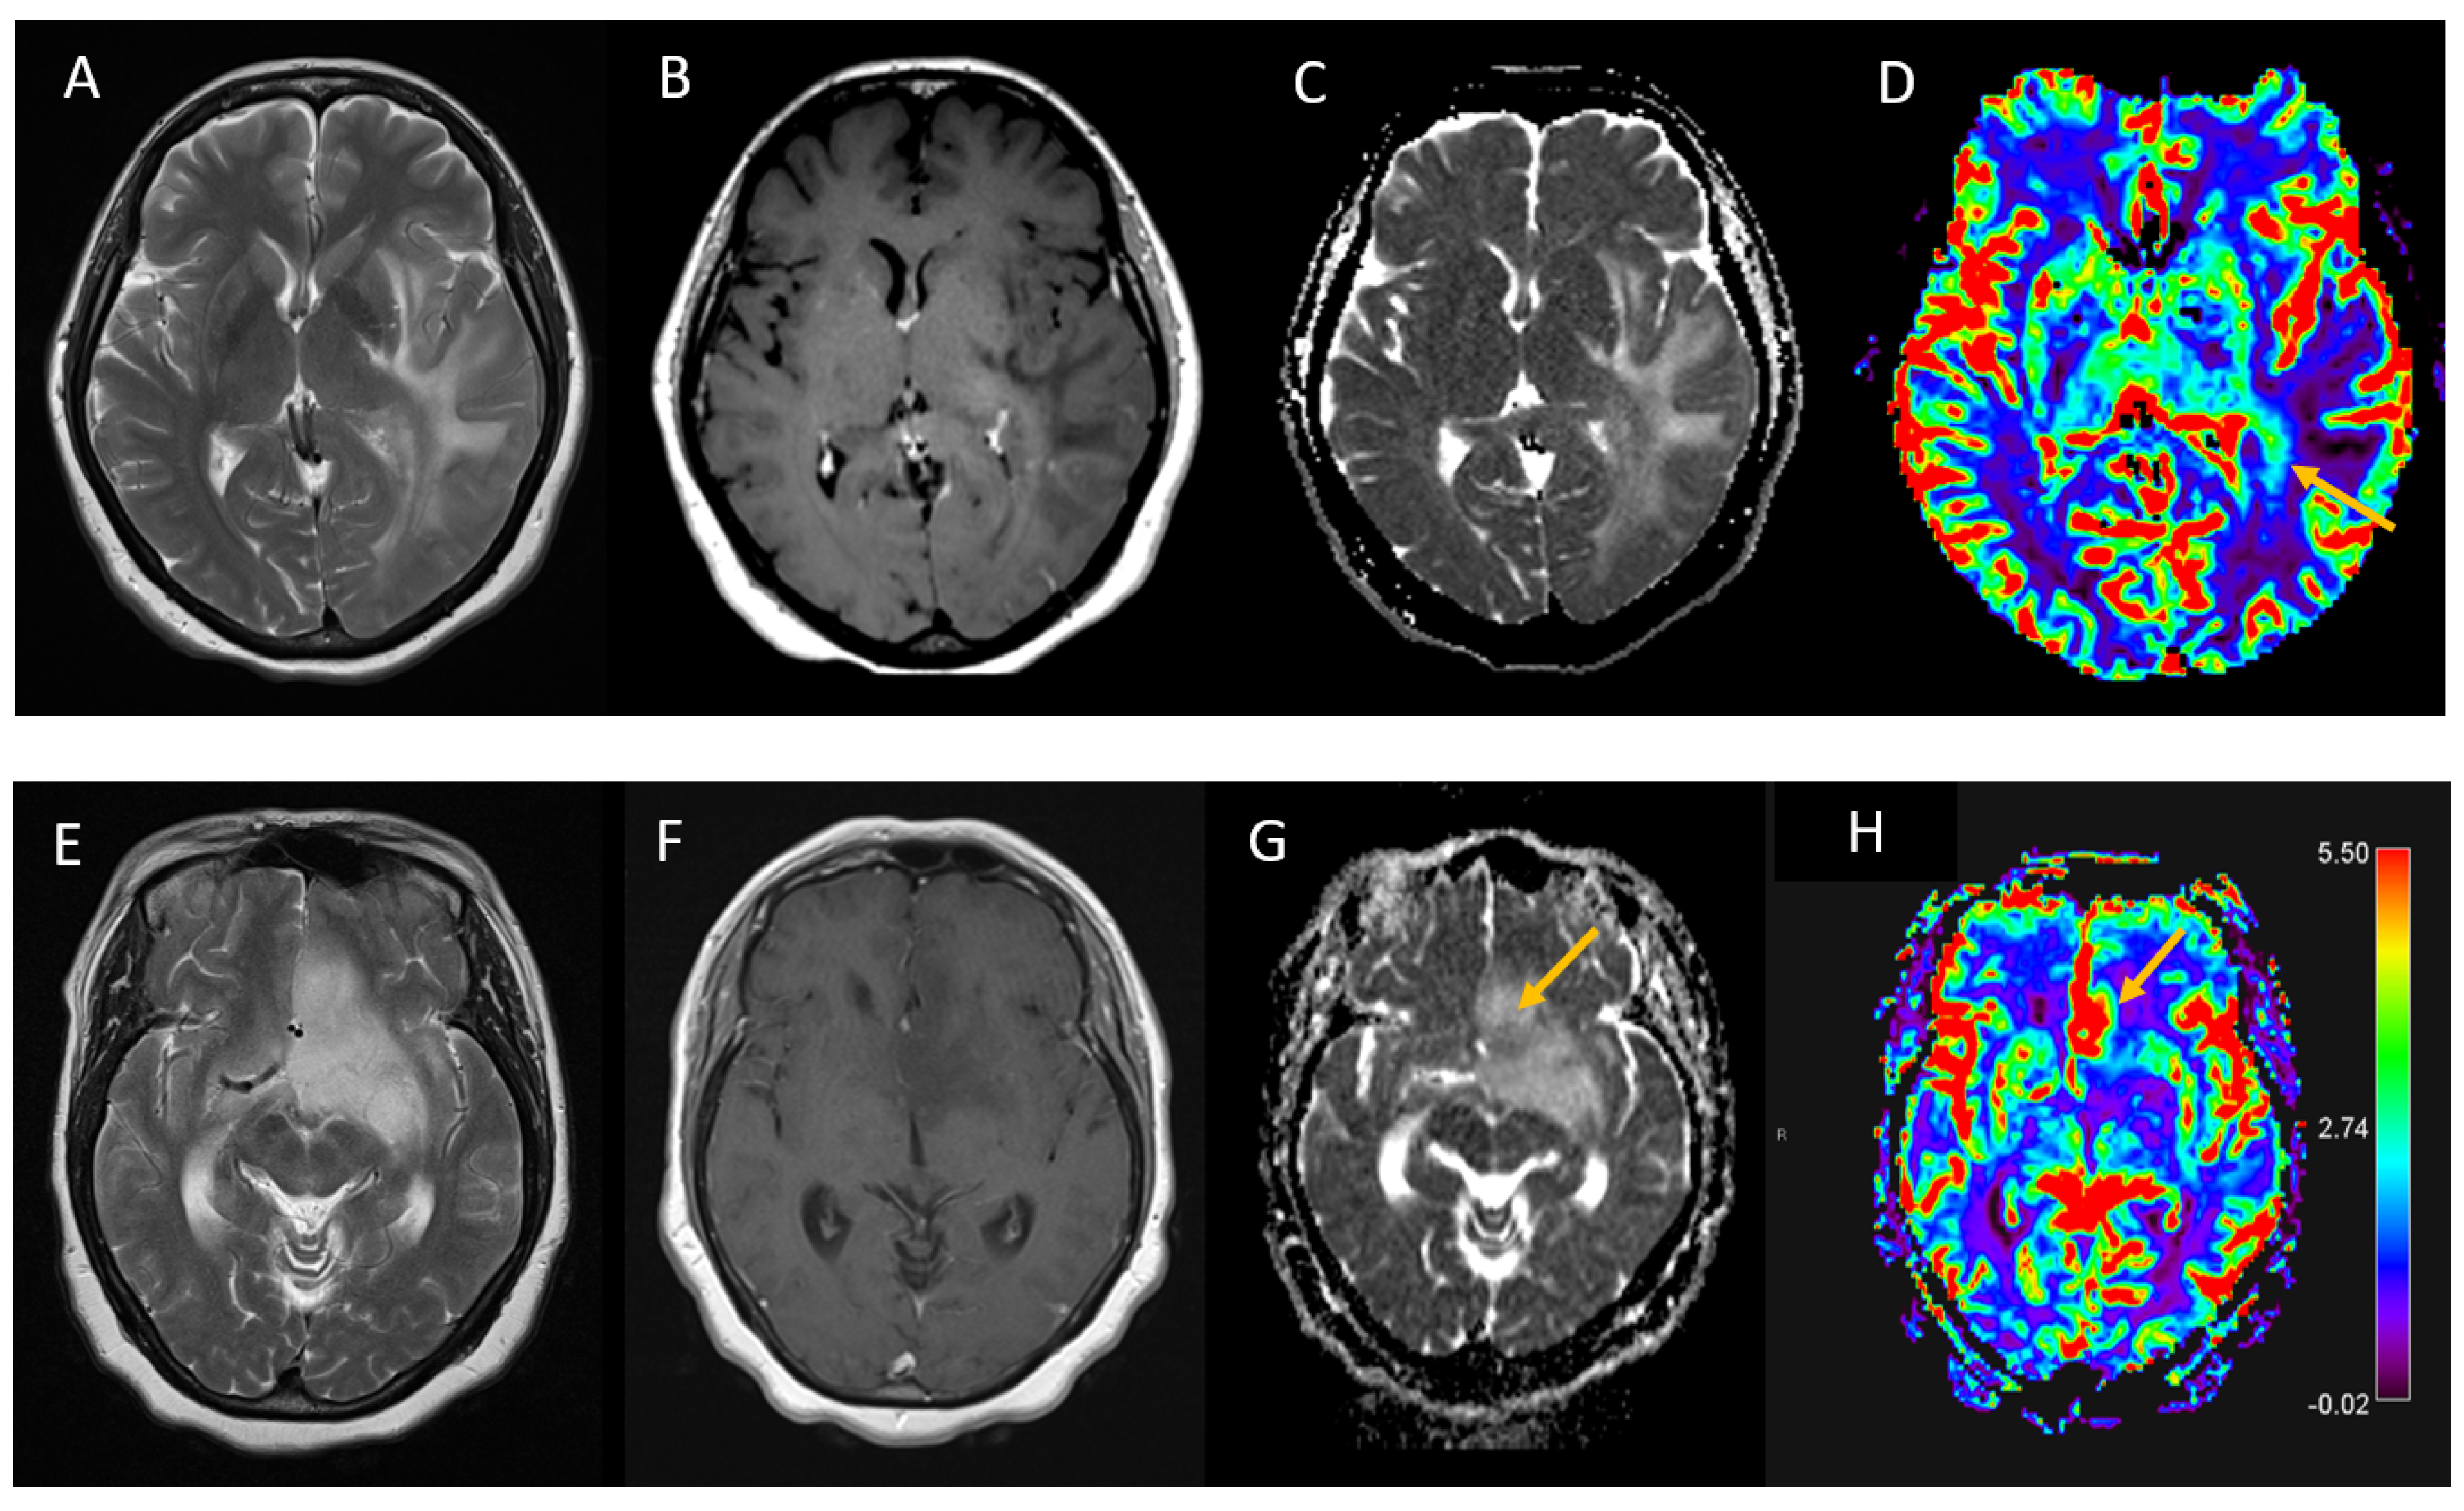

3.2. Imaging Tumour Characteristics

| Median lowest ADCmean within the tumour (×10−3 mm2/s, IQR) | 0.81 | 0.64 to 0.90 |

| Median ADCmean within the tumour (×10−3 mm2/s, SD) | 0.97 | 0.87 to 1.01 |

| Median ADCmean in normal white matter (×10−3 mm2/s, SD) | 0.75 | 0.73 to 0.82 |

| Advanced imaging performed (DSC perfusion or MRS) (n, %) | 8 | (28%) |